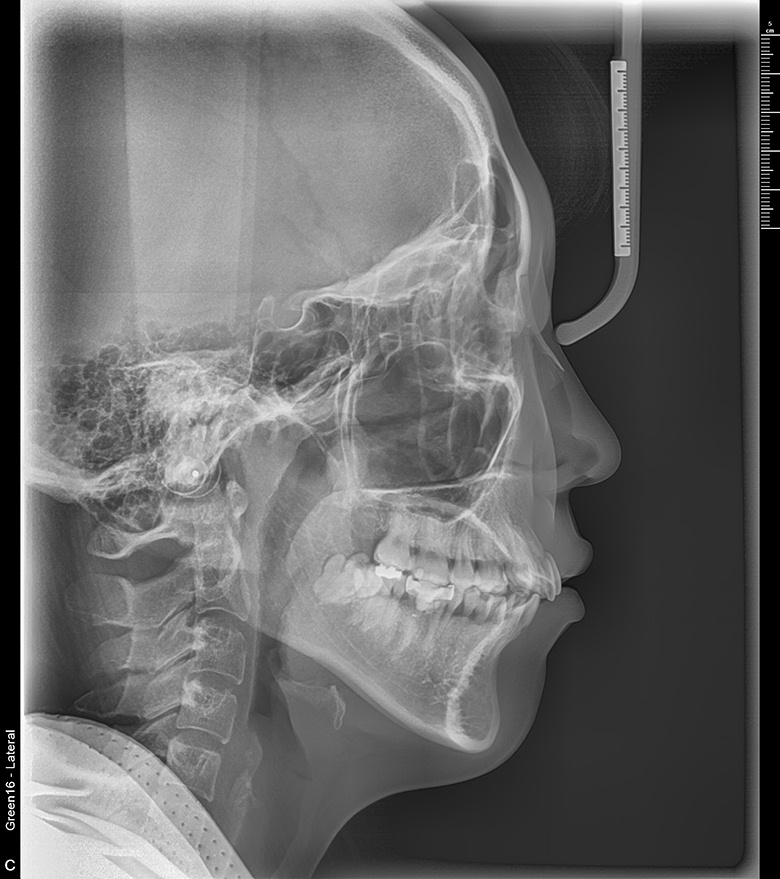

치료 전 사진입니다.